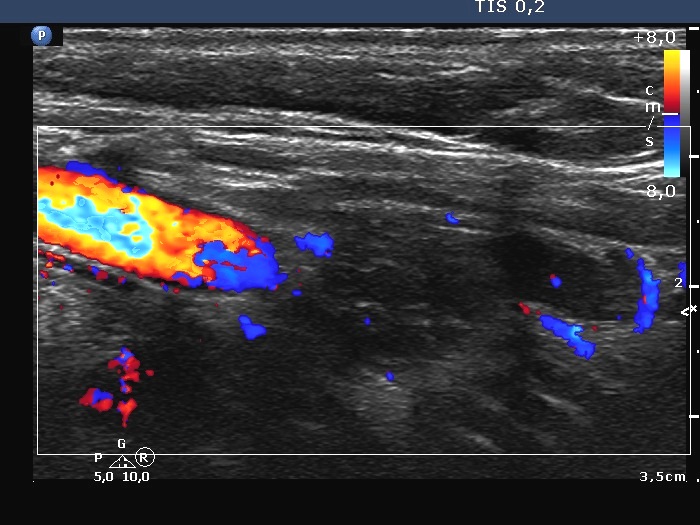

The role of complex diagnosis - follicular proliferation - Case 7. (ultrasonographic picture 9)

Left lobe, longitudinal scan, color Doppler mode. The vascularization is not specific.